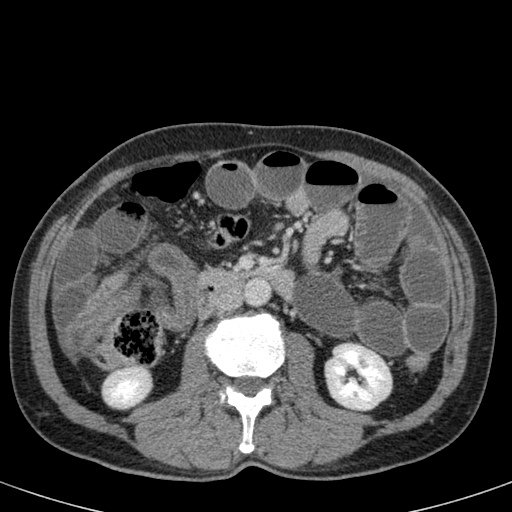

Đây là một bệnh nhân bị tắc ruột non.

Cuộn qua các hình ảnh.

Bạn có thể tìm thấy quai kín và nguyên nhân gây ra nó không?

CT là phương pháp chẩn đoán hình ảnh được lựa chọn trong đánh giá bệnh nhân nghi ngờ tắc ruột non.

Nếu quai kín ngắn và nằm trong mặt phẳng tạo ảnh, chúng ta sẽ thấy quai ruột hình chữ U hoặc chữ C.

Tắc ruột dạng quai kín với các quai ruột giãn xếp theo hình nan hoa. Có dày thành ruột và phù nề mạc treo gợi ý thiếu máu cục bộ

Một hình ảnh quan trọng khác của tắc ruột dạng quai kín là các quai ruột non giãn xếp theo hình nan hoa với các mạch máu mạc treo hội tụ về một điểm trung tâm.

Hình ảnh này hầu như luôn do xoắn ruột non gây ra.